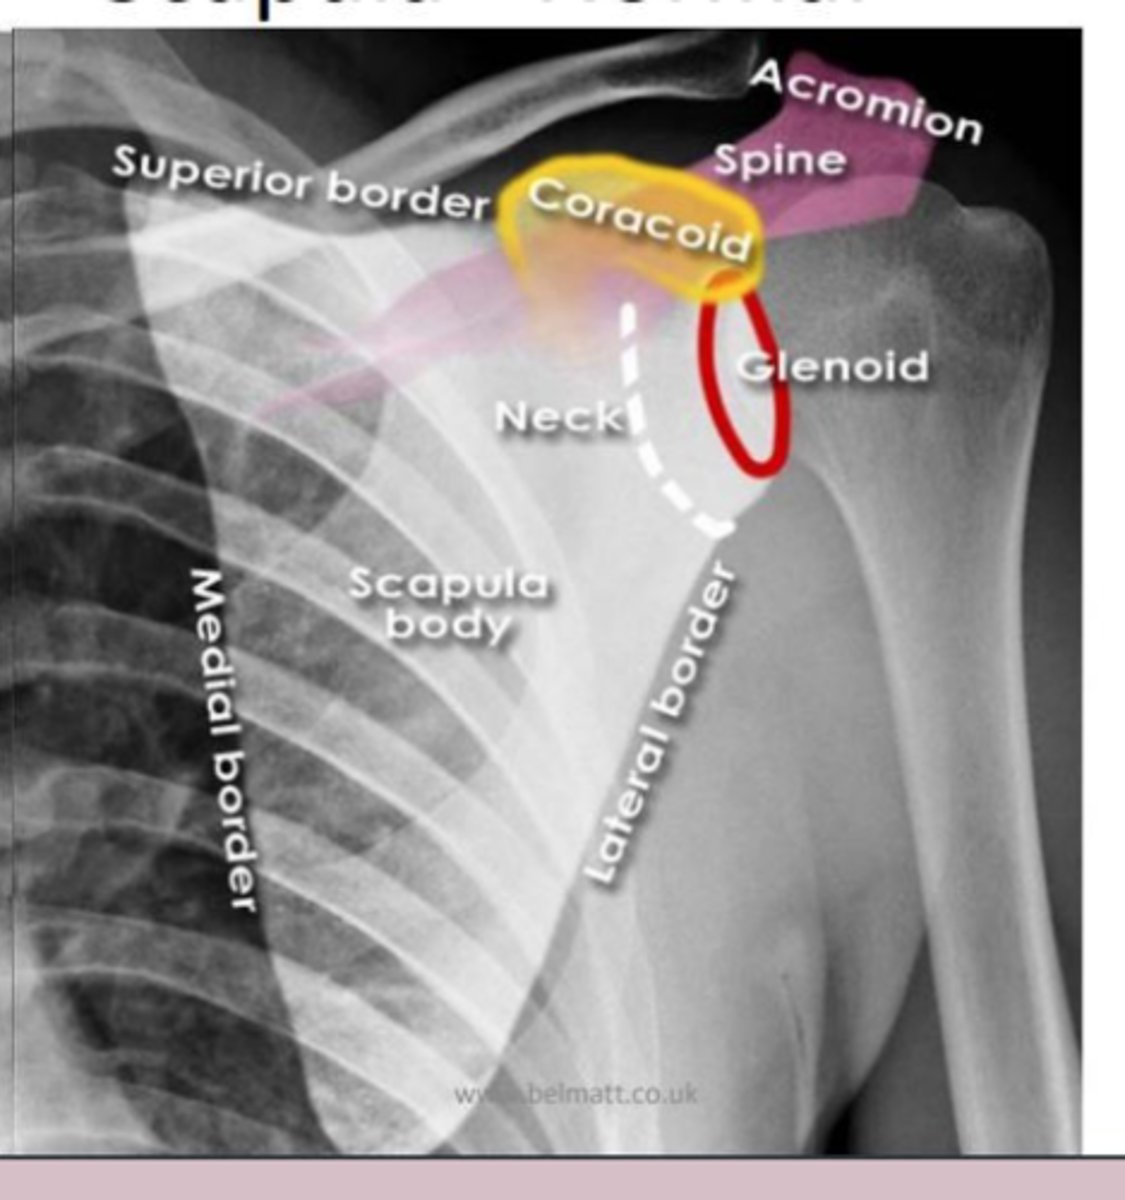

scapula

knowt flashcard image